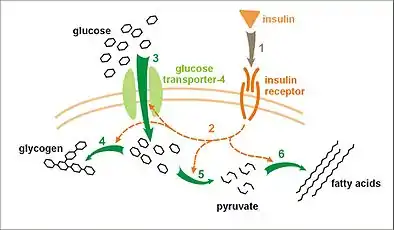

The Insulin Receptor is a type of tyrosine kinase receptor, in which the binding of an agonistic ligand triggers autophosphorylation of the tyrosine residues, with each subunit phosphorylating its partner. The addition of the phosphate groups generates a binding site for the insulin receptor substrate (IRS-1), which is subsequently activated via phosphorylation. The activated IRS-1 initiates the signal transduction pathway and binds to phosphoinositide 3-kinase (PI3K), in turn causing its activation. This then catalyses the conversion of Phosphatidylinositol 4,5-bisphosphate into Phosphatidylinositol 3,4,5-trisphosphate (PIP3). PIP3 acts as a secondary messenger and induces the activation of phosphatidylinositol dependent protein kinase, which then activates several other kinases – most notably protein kinase B, (PKB, also known as Akt). PKB triggers the translocation of glucose transporter (GLUT4) containing vesicles to the cell membrane, via the activation of SNARE proteins, to facilitate the diffusion of glucose into the cell. PKB also phosphorylates and inhibits glycogen synthase kinase, which is an enzyme that inhibits glycogen synthase. Therefore, PKB acts to start the process of glycogenesis, which ultimately reduces blood-glucose concentration.[17]

Effect of insulin on glucose uptake and metabolism. Insulin binds to its receptor (1), which, in turn, starts many protein activation cascades (2). These include: translocation of Glut-4 transporter to the plasma membrane and influx of glucose (3), glycogen synthesis (4), glycolysis (5), and fatty acid synthesis (6).

Effect of insulin on glucose uptake and metabolism. Insulin binds to its receptor (1), which, in turn, starts many protein activation cascades (2). These include: translocation of Glut-4 transporter to the plasma membrane and influx of glucose (3), glycogen synthesis (4), glycolysis (5), and fatty acid synthesis (6). Signal transduction of Insulin: At the end of the transduction process, the activated protein binds to the PIP2 proteins embedded in the membrane.